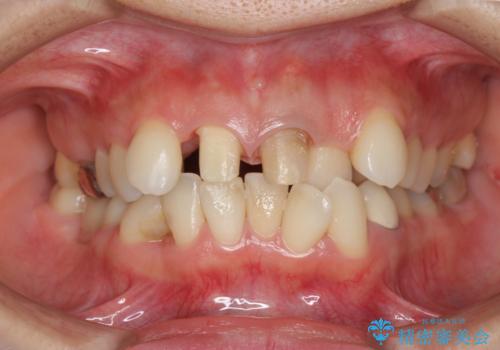

子供の頃にぶつけた前歯 根管治療から行うセラミック治療

- 幼少時にぶつけ、神経を取った歯の審美改善を求めて来院されました。

X線写真より不十分な根管治療、根尖病変、前歯の変色が認められます。

歯根の近接のみられる右上側切歯を抜去し、根管治療を伴うセラミック治療を計画します。